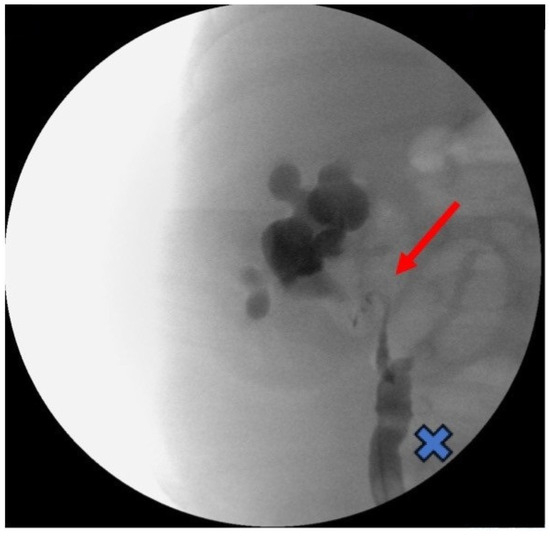

Therefore, three months after the acute spontaneous pelvic rupture, the baby boy underwent a combined minimally invasive treatment composed of cystoscopic high-pressure balloon dilatation (HPBD) for the UVJO and one-trocar-assisted pyeloplasty for the PUJO that required a minimal widening of the flank incision up to 2.5 cm. During the postoperative follow-up, there were no signs of urinary tract infection, and there was an improvement in urine drainage, with no evidence of hydroureteronephrosis. The latest ultrasound examination revealed that the right kidney displayed normal corticomedullary differentiation, maintained cortical thickness, and exhibited minimal presence of the renal pelvis, approximately measuring 5–6 mm. Additionally, there was no dilation observed in the kidney’s calyces or ureter (Figure 4).

Figure 4.

US 8 months after surgery showing the right kidney with regular cortico-medullary differentiation, preserved cortical thickness, renal pelvis of approximately 5–6 mm, and no dilation of the calyces or the ureter.